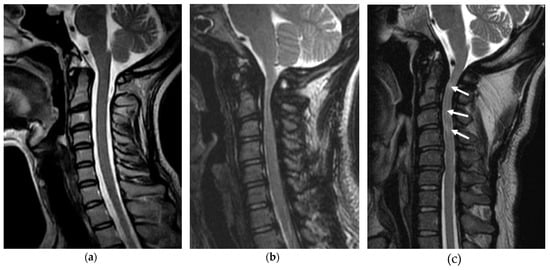

2.1.2. Cervical Stenosis